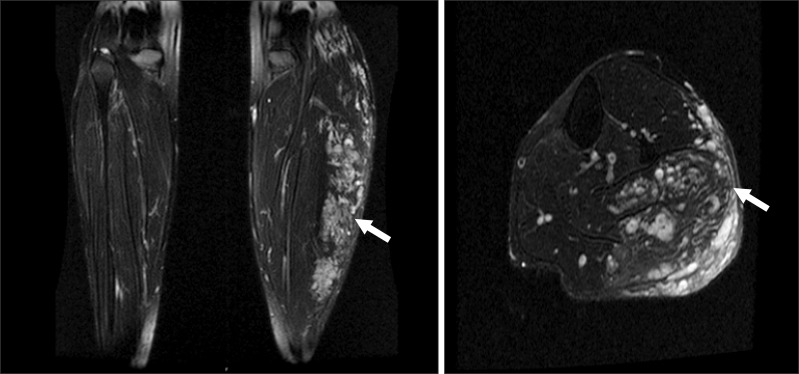

A 31-year-old female patient with a height of 164 cm and weight of 60 kg was admitted to undergo ethanol sclerotherapy for a large painful vascular malformation in her left leg. Magnetic resonance imaging revealed an AVM measuring 28 × 7 × 4 cm in her left calf (Fig. 1). All preoperative examinations, including laboratory tests, electrocardiography, and chest X-ray, were normal. Vital signs before general anesthesia were stable: her blood pressure was 130/80 mmHg and her heart rate was 82 beats/min. Following the application of routine hemodynamic monitoring (3-lead electrocardiogram, noninvasive blood pressure, and pulse oximetry), anesthesia was induced using a bolus intravenous injection of 120 mg propofol and 40 mg rocuronium. A 20-gauge catheter was inserted into the radial artery to monitor her arterial blood pressure continuously. The target controlled infusion of 2% propofol and remifentanil (2-3 µg/ml and 2-5 ng/ml of the effect-site concentrations, respectively) was applied to maintain anesthesia. Immediately following the injection of ethanol, the patient's blood pressure and heart rate rose slightly to 160/100 mmHg and 100 beats/min, respectively. Thereafter, the patient's blood pressure and heart rate were stable throughout the procedure while she was in the prone position. A total dose of 50 ml of 99% ethanol was injected into the lesion over a period of 30 minutes without the use of a tourniquet. As soon as the patient was turned from prone to supine after finishing the procedure, an abrupt drop in her arterial blood pressure occurred, 40-50 mmHg systolic and 10-15 mmHg diastolic blood pressure with a simultaneous increase in her heart rate to 100-110 beats/min. To restore blood pressure, 20 mg of ephedrine was immediately injected, but the patient's heart rate rather decreased abruptly to < 30 beats/min. Chest compressions were performed along with the simultaneous injection of 50 µg of epinephrine. A few minutes later, the patient's blood pressure and heart rate recovered to 180/100 mmHg and 100-110 beats/min. At that moment, the arterial blood gas analysis showed metabolic acidosis with otherwise normal findings (pH 7.29, PaCO2 28 mmHg, PaO2 466 mmHg, SaO2 100%, base excess -11.6, Hematocrit 38%, Na+ 137 mEq/l, K+ 3.7 mEq/l, and Ca2+ 1.11 mmol/l). The patient was transferred to the intensive care unit with the endotracheal tube in place. Transthoracic echocardiograph (TTE) and embolism computed tomography (CT) were performed to confirm pulmonary hypertension or pulmonary embolism. There was no evidence of pulmonary embolism on CT. In addition, the peak tricuspid regurgitation jet velocity on TTE was 2.3 m/s, indicating no evidence of pulmonary hypertension at that moment (Fig. 2A). However, TTE revealed dilated right ventricle (Fig. 2B) and severely decreased right ventricular function.